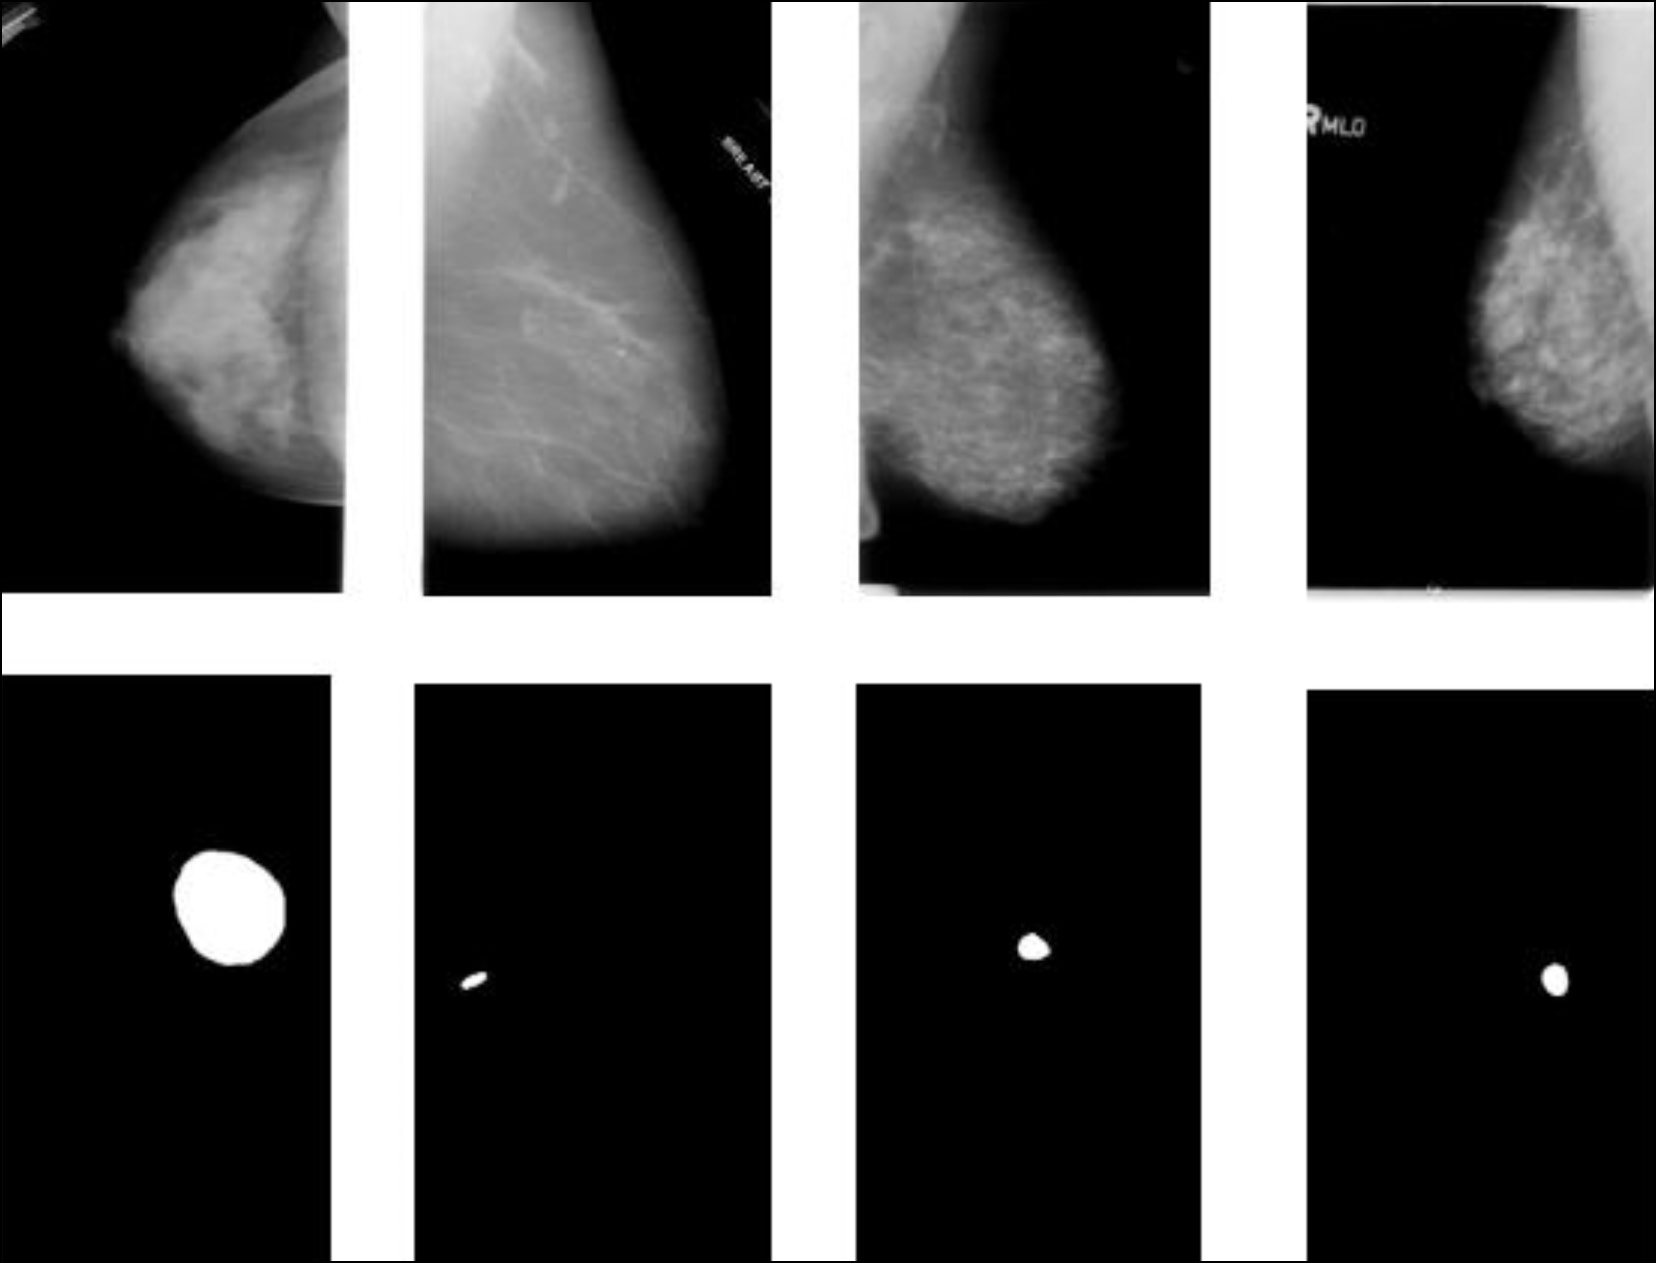

- Raza SK, Sarwar SS, Syed SM, Khan NA. Classification and Segmentation of Breast Tumor Using Mask R- CNN on Mammograms. Research Square. 2021. doi: 10.21203/rs.3.rs-523546/v1

- Tsochatzidis L, Costaridou L, Pratikakis I. Deep Learning for Breast Cancer Diagnosis from Mammograms – A Comparative Study. Journal of Imaging. 2019;5(3):37. doi: 10.3390/jimaging5030037

- Ruchai AN, Kober VI, Dorofeev KA, et al. Classification of breast pathologies using a deep convolutional neural network and transfer learning. Information processes. 2020;20(4):357–365.

- Sasov DA, Zubkov AV, Orlova YuA, Tupitsyna AV. Classification of breast cancer using convolutional neural networks. Inženernyj vestnik Dona. 2023;6:730–741. (In Russ.)